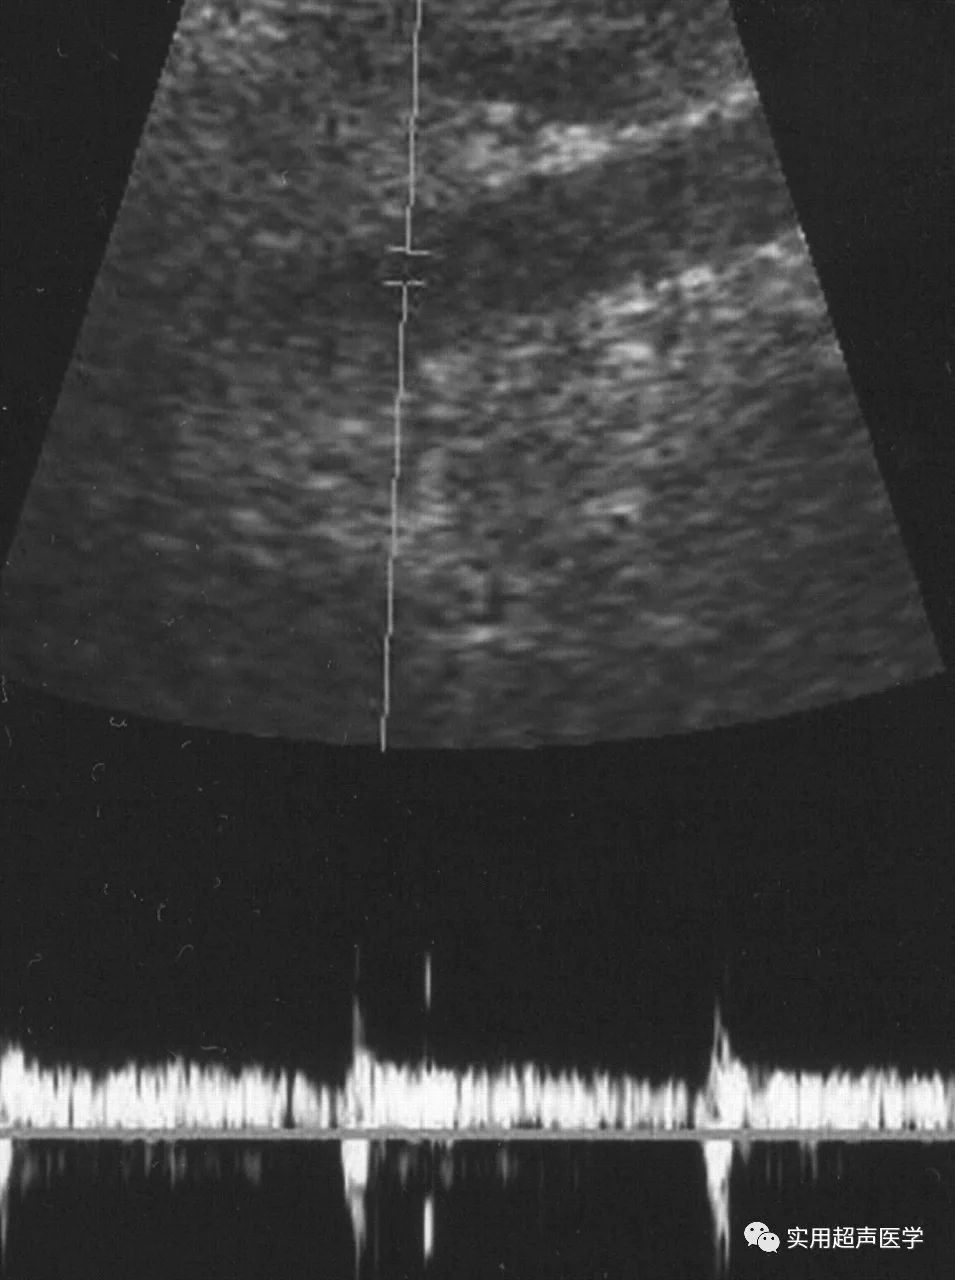

38岁女性盆腔充血综合征患者。扩张型卵巢静脉丛的多普勒超声检查显示,Valsalva 的手法没有改变血流方向和强度。

38岁女性盆腔充血综合征患者。扩张卵巢静脉丛的多普勒超声检查显示,Valsalva 手法最初加重。

最近的一份报告表明,Valsalva手术期间盆腔精索静脉曲张的初始加重是诊断盆腔充血综合征的重要多普勒超声检查发现,类似于男性阴囊精索静脉曲张的诊断方法。在男性中,Valsalva操作期间扩张静脉的初始血流增压对于诊断阴囊精索静脉曲张很重要。由于阴囊精索静脉曲张位于腹膜腔外,如果 Valsalva 操作期间腹膜压力升高,阴囊精索静脉曲张中的突然血流充盈会使多普勒超声检查显示初始血流增强。由于女性的盆腔精索静脉曲张是腹腔内的,因此在盆腔充血综合征患者的Valsalva操作过程中会出现可变的多普勒波形。在Valsalva操作过程中,扩张盆腔静脉中多普勒波形的可变变化,包括初始增强,流型无变化,流向逆转和血流突然消失。多普勒超声检查显示的血流方向逆转和突然消失分别与选择性卵巢静脉造影的反流和淤滞相关。